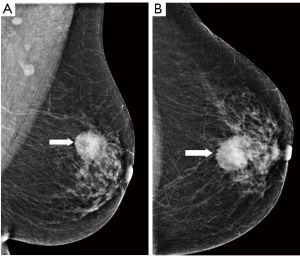

Figure 10 Mammography of the left breast in cranio-caudal view (A) with architectural distortion (arrow). The distortion is more visible in DBT (B) (arrow). Ultrasound (C) reveals subtle finding of irregular area of decreased echogenicity (arrow). MRI (D) shows extensive area of non-mass-like enhancement in the whole lateral part of the breast (arrow). DBT, digital breast tomosynthesis; MRI, magnetic resonance imaging. - Diagnostic assessment, a patient of 45 years of age with a palpable lump on the right side for 2 months. In mammography with higher proportion of fibroglandular tissue (category C) several areas of increased density with irregular margins and architectural distortions are visible. Ultrasound confirms more than one lesion. MRI demonstrates a large area of enhancement up to 7 cm (Figure 11).

Figure 11 Mammography of the right breast in medio-lateral-oblique (A) and cranio-caudal view (B) with multiple densities with irregular margins and architectural distortions (arrows). Ultrasound (C) shows more than two hypoechoic lesions of suspicious features. In MRI (D) an extensive area of tumour involvement is revealed. MRI, magnetic resonance imaging. - A patient of 50 years of age evaluated for enlarged lymph nodes in the axilla. Mammography and ultrasound show enlarged pathological lymph nodes in the axilla, otherwise no pathological finding in the breast on initial evaluation despite the low mammographic density. The largest lymph node is biopsied proving metastatic invasive carcinoma NST of breast origin. MRI is indicated to search for an occult lesion in the breast. MRI shows the enlarged lymph nodes and a small lesion in the right breast in upper outer quadrant. A second-look, targeted ultrasound with the knowledge of the location of the lesion is performed to reveal a small suspicious lesion, which is subsequently verified as the primary tumour in the breast (Figure 12).